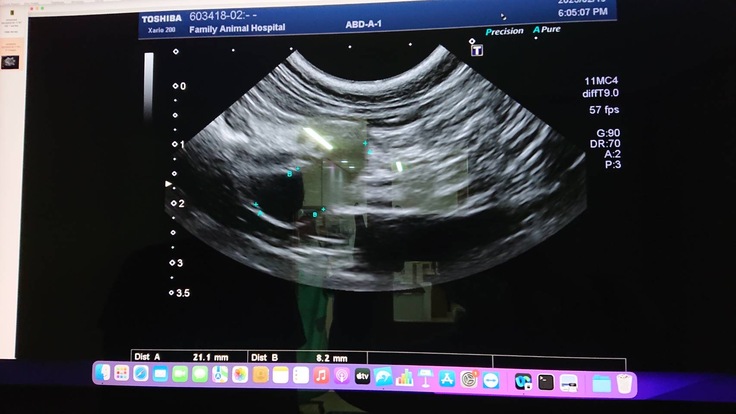

2月19日病院を受診し、血液検査、エコー検査をしたところ胸水に水が溜まっており抜いたところ黄疸が出でおりほぼFIPの可能性が高くなりました。

検査・診察代:血液検査、エコーなど1回あたりおおよそ2万円×7回=140,000円